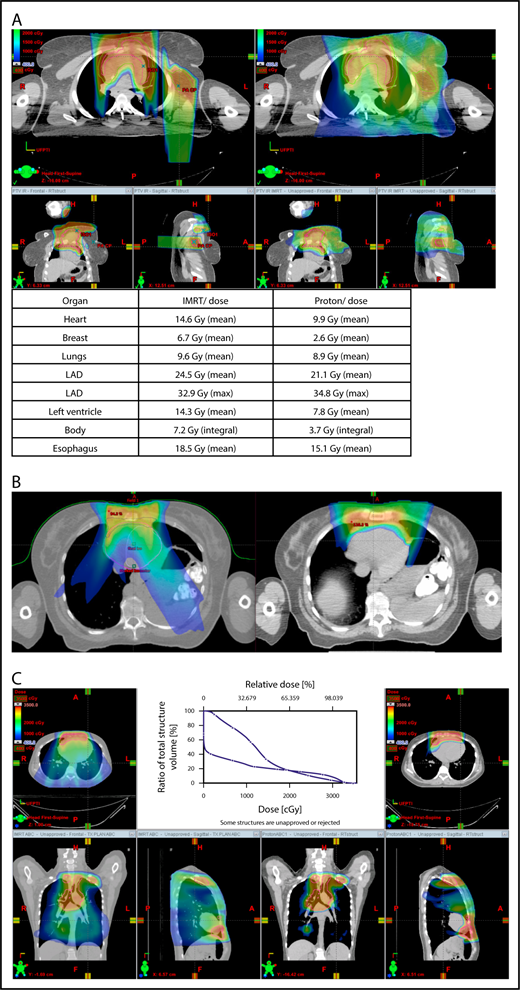

Proton therapy can significantly reduce the radiation dose to the breasts by specifically using fields that enter posteriorly and stop short of exiting through the breast. Alternatively, if protons cannot be used, other methods of displacing the breast can be used instead, such as using an inclined board or physically moving the breast out the beam path. Figure 3A shows how using proton therapy can spare the breast in a case with axillary involvement.

Axillary involvement at presentation. (A) Axial, coronal, and sagittal views of a proton plan (left) and an IMRT plan (right) for a patient presenting with axillary involvement. Use of proton therapy in this case spares the left breast. (B) Regardless of which treatment modality is chosen, IMRT (left panel) and proton (right panel), limiting the volume exposed to radiation should include attention to avoiding a low-dose bath. (C) Limiting lung dose. If avoiding the lung is the primary objective in a given patient, especially if the patient has received pulmonary toxic chemotherapy (eg, any combination of bleomycin, busulfan, gemcitabine, brentuximab, etc.), proton therapy may better spare the lungs by reducing the low-dose bath seen with photons.

When hilar disease needs to be covered, the dose to the breasts can increase, and avoiding the breasts becomes difficult with either modality (proton or photon). The choice of treatment modality for such cases must consider the doses received by other critical structures, such as the heart and lungs, especially in previously and heavily treated patients. However, in considering how to best limit the volumes exposed to radiation, avoiding “low-dose baths” is equally important (ie, irradiation of large volumes with low doses), regardless of which modality is used (Figure 3B).

Consideration of lung dose

With the advent of CT-based planning for mediastinal lymphoma, the dose to the lungs can now be correlated with the risk for pneumonitis. Restrictions on lung dose are encouraged to be V5 < 55%, mean lung dose < 13.5 Gy, and V30 < 20%. These values are more attainable with the use of DIBH.38 Although a mean lung dose of 13.5 Gy has been associated with a lower risk for pneumonitis, it is advisable to aim for a lower dose, which is quite often attainable when strict constraints are used. For example, when IMRT is used, it is important to limit the beams to some variation of anteroposterior beams, avoiding lateral beams. If avoiding the lung is the primary objective for a given patient, especially if that patient has received pulmonary-toxic chemotherapy (eg, bleomycin, busulfan, gemcitabine, brentuximab), proton therapy may better spare the lungs by reducing the low-dose bath seen with photons (Figure 3C).